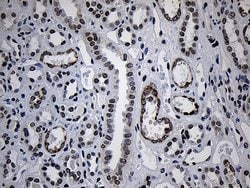

ZNF670 Monoclonal Antibody for Western Blot, IHC (P)

| Immunohistochemistry (Paraffin), Western Blot | |